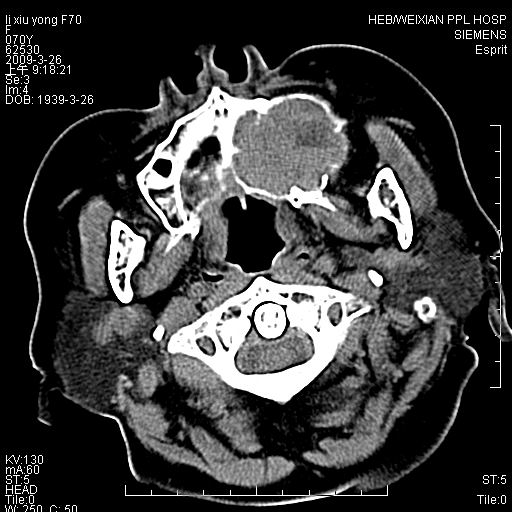

老年患者,女。鼻塞多年。

考虑右侧上颌窦良性占位性病变,粘液囊肿可能性大;建议活检。

膨胀性生长,且骨质无破坏,说明时间久,良性;从密度,边缘看,内部还见坏死区,应该是实性肿瘤,定性,影像学无绝对的特异性

病灶密度很不均匀,骨壁膨胀中有断裂,考虑内翻乳头状瘤可能性大,粘液囊肿不排除

膨胀性生长,且骨质无破坏,说明时间久,良性;从密度,边缘看,内部还见坏死区,应该是实性肿瘤,定性,影像学无绝对的特异性,考虑内翻性乳头状瘤可能